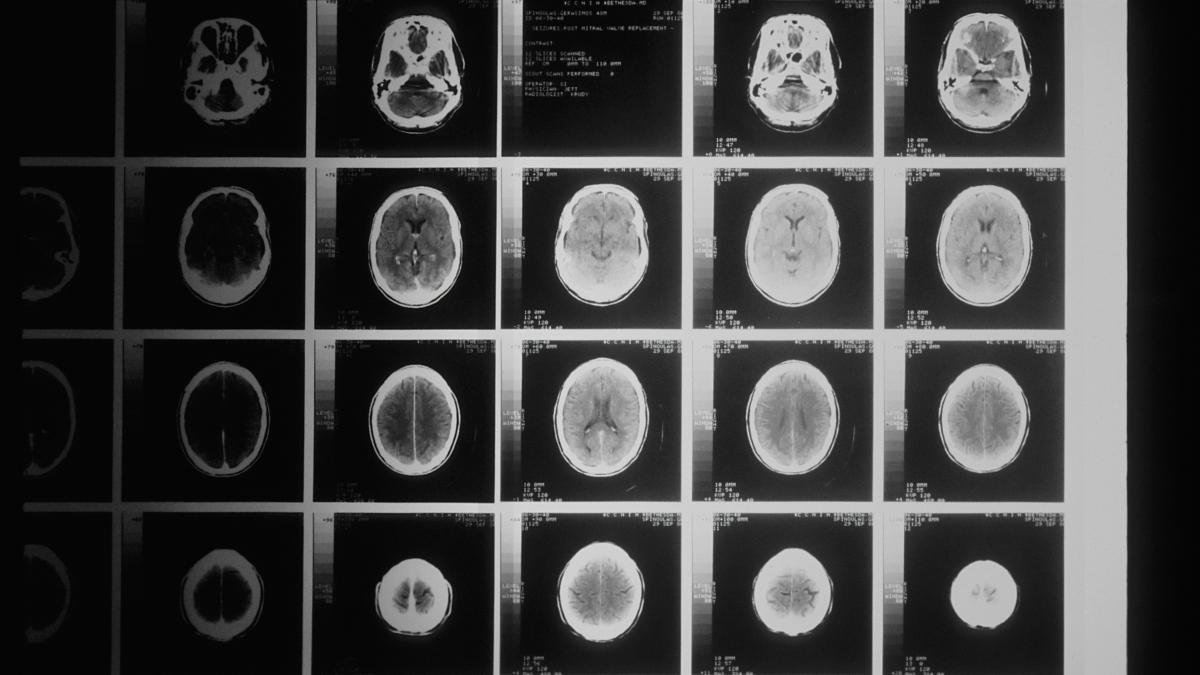

Un diagnostic corect și detaliat este esențial pentru succesul tratamentului. Dr. Nica subliniază că investigațiile imagistice avansate ajută la identificarea clară a tumorii și la stabilirea unui plan chirurgical personalizat.

„Ajutorul endoscopiei, deci poți să faci o operație cu microscopul dar să fii ajutat și endoscopic în profunzime pentru că tu te duci cu vederea fix acolo prin intermediul endoscopului, dar și cu lumina tot fix acolo. Nu putem intra acolo fără să nu avem un computer tomograf nativ și cu substanță de contrast pentru că sunt tumori care prind mai mult contrastul și delimitează sau prezintă oarecum o parte a structurii tumorii gen necroză sau chist în interiorul tumorii

Rezonanța magnetică nucleară care a evoluat foarte mult, acum avem 3 Tesla la Sanador, așa, înseamnă o finețe a imaginilor și o claritate a imaginilor mult mai bună decât cu 1,5 Tesla

Aceste RMN-uri sunt și cu câteva programe interesante printre care mai nou mai nou sunt Diffuse Tensor Imaging DTI, adică arată clar, poate să ne arate tracturile importante, adică cele care pleacă de la creier și se duc către periferie ca să putem să comandăm mișcările și cele care vin dinspre periferie să ajungă la creier ca să avem senzațiile respective. Deci totul se vede și atunci, în funcție de localizarea tumorii, poți să te duci foarte clar, precis să știi să eviți anumite zone să nu le lezezi, să știi cam care sunt marginile tumorii, să știi să ocolești tracturile respective ca să nu produci leziuni mai multe decât a produs tumora sau edemu din jurul tumorii”, încheie medicul de la Sanador.